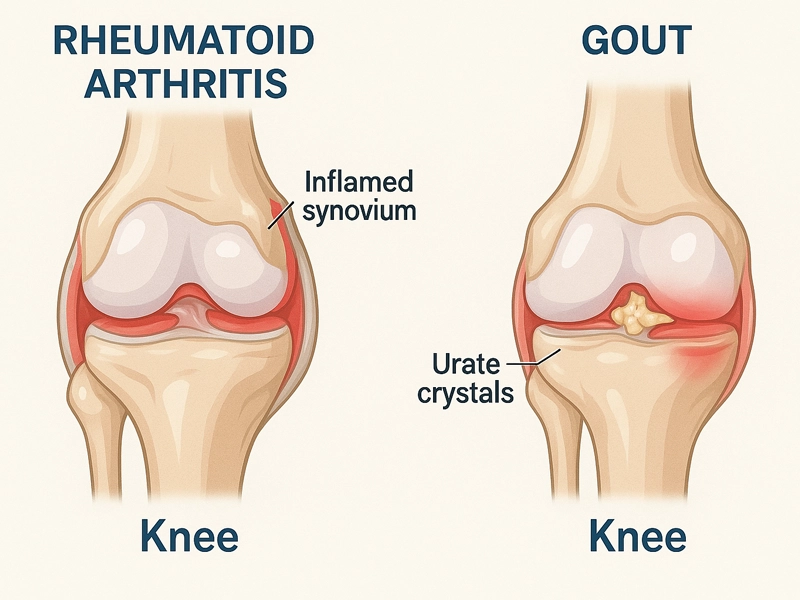

درد و التهاب در زانو ممکن است به دلایل مختلفی ایجاد شود، اما دو مورد از مهمترین آنها، روماتیسم مفصلی زانو و نقرس زانو هستند. این دو بیماری، گرچه هردو باعث درد، ورم و ناراحتی در ناحیه زانو میشوند، اما در واقعیت، تفاوتهای بسیار مهمی در علت، علائم، سیر بیماری و درمان دارند. در این […]